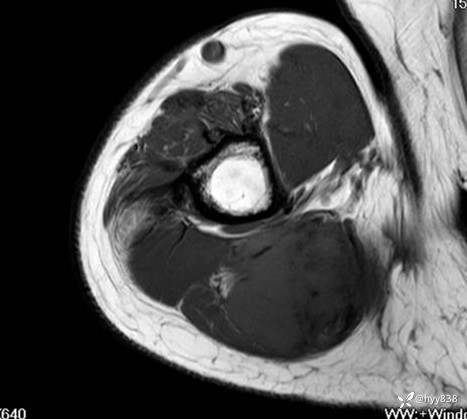

MRI AXI T1WI+T2WIfs

AXI T1WI+T2WIfs